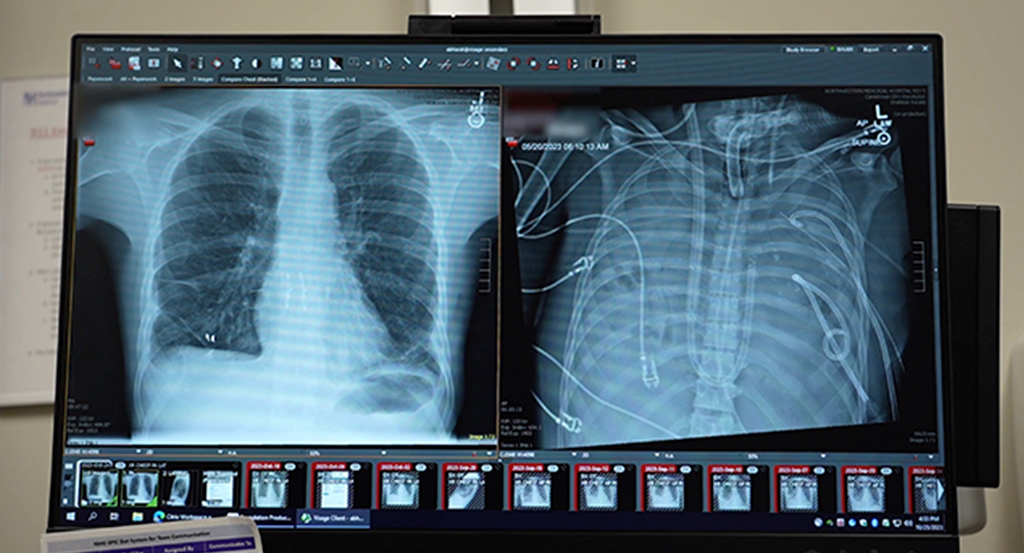

A equipe médica da Universidade Northwestern, nos Estados Unidos, manteve um paciente vivo sem seus dois pulmões por 48 horas, na espera de um transplante. O feito só foi possível graças a um sistema de pulmão artificial total (Total Artificial Lung – TAL), desenvolvido pela própria universidade.

O pulmão artificial TAL foi projetado para substituir temporariamente as principais funções dos pulmões reais, como a oxigenação do sangue. Mais do que isso, a máquina mantém o fluxo sanguíneo equilibrado, estabilizando o estado clínico do paciente e o preparando para receber os novos órgãos.

O sistema artificial é adaptativo ao fluxo, o que compensa a perda da rede de vasos sanguíneos pulmonares. Ele também inclui canais duplos que drenam o sangue do corpo e devolvem ao coração o sangue oxigenado. Também foram usados suportes internos temporários para impedir o deslocamento do coração, que ficaria sem sustentação após a retirada dos pulmões.

Com essa inovação, os médicos mantiveram homem vivo por dois dias após a remoção dos pulmões. Durante esse período, sua condição apresentou melhoras significativas e o organismo começou a se recuperar da infecção, reduzindo os riscos do transplante.